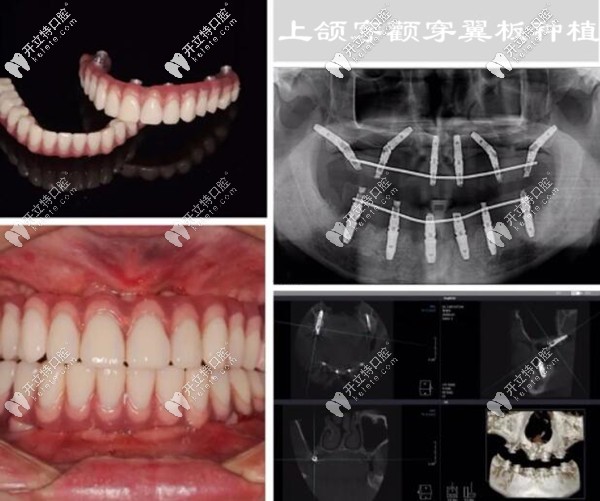

沒(méi)有對(duì)比就沒(méi)有傷害,下面是我做全口種植牙前后的照片,誰(shuí)能想到這是同一個(gè)人▼

其實(shí),手術(shù)前我很緊張、也很擔(dān)心,怕手術(shù)有風(fēng)險(xiǎn)~~~~在登緹斯口腔的種植醫(yī)生團(tuán)隊(duì)的配合下,做了術(shù)前的仔細(xì)、周密準(zhǔn)備,從拔殘牙根開(kāi)始,用了兩個(gè)多小時(shí);手術(shù)挺順利、術(shù)后就戴了臨時(shí)牙冠,從術(shù)后的CT片上能看出每顆種植體的位置都很精準(zhǔn)。